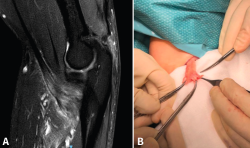

Las lesiones del tendón distal del bíceps varían desde la bursitis bicipitorradial hasta las roturas completas, pasando por las tendinosis y las lesiones parciales. Una buena historia clínica y una exploración física meticulosa aportan gran cantidad de información a la hora de orientar el diagnóstico, que se puede apoyar en la ecografía y la resonancia nuclear magnética para confirmar el diagnóstico y descartar otras entidades plausibles. En el caso de la bursitis bicipitorradial, la tendinosis y las lesiones parciales, el tratamiento inicial debe ser conservador salvo en casos concretos. Las roturas completas agudas deben tratarse de forma quirúrgica excepto en pacientes con baja demanda física o no aptos para tratamiento quirúrgico, sin sobrepasar las 4 semanas de evolución. En caso de diagnóstico tardío y roturas crónicas, las alternativas son la reparación primaria o la reconstrucción con autoinjerto o aloinjerto. Tras la cirugía, es imprescindible seguir un protocolo de rehabilitación que progrese en la ganancia del balance articular y la fuerza sin alterar el proceso de cicatrización. El objetivo de este artículo es presentar las distintas lesiones del bíceps distal, los métodos diagnósticos más adecuados y las alternativas terapéuticas para cada una de las entidades patológicas, para lo que se ha llevado a cabo una revisión bibliográfica a través del motor de búsqueda PubMed de artículos en inglés con referencia al tema seleccionado.

Distal biceps tendon injuries vary from bicipitoradial bursitis to complete rupture, including tendinosis and partial rupture. A good patient history and physical examination provide a great amount of information when trying to establish diagnosis helped by ultrasound and MRI to confirm our suspicion and make a differential diagnosis. Initial treatment for bicipitoradial bursitis, tendinosis and partial rupture should be conservative except in some concrete patients. Complete acute ruptures should be managed by surgical treatment except in low demand patients or patients with concerns regarding anesthesia or surgery. This surgery should be performed before 4 weeks after initial trauma. In case of delayed diagnosis or chronic ruptures, the different alternatives are primary reparation or reconstruction with autograft or allograft. After surgery a rehabilitation program is essential to improve range of motion and strength without stressing the healing process. The main purpose of this manuscript is to present different distal biceps injuries, the most adequate ways to establish a diagnosis and treatment alternatives for every kind of lesion. That is why a revision has been performed through PubMed search engine regarding the selected issue.